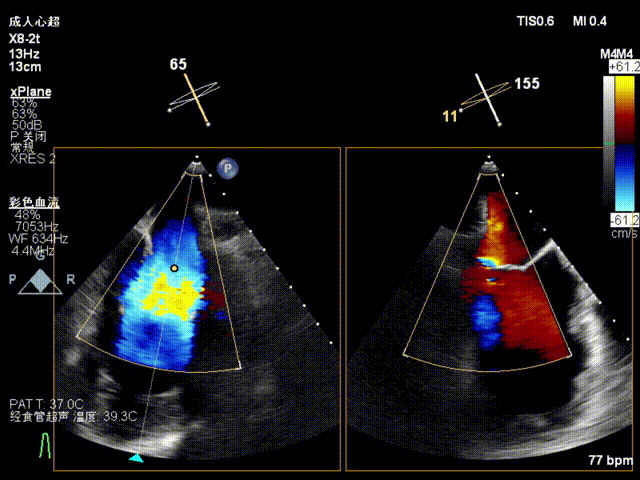

本例患者为北京安贞医院首例正式入组病例,该患者为71岁老年男性,高血压病史两年,合并动脉粥样硬化,高血脂症病史,因“阵发性呼吸困难半年”就诊,经充分标准化药物治疗后仍有相关症状。超声心动图提示重度二尖瓣返流(MR 4+),可见二尖瓣后叶栓系,有效返流口面积为0.38cm²,返流量63mL,瓣口面积为6.7cm²;轻度三尖瓣返流;轻度主动脉瓣返流;LVEDD 57mm,LVESD 42mm,LVEF 44%。诊断考虑为重度功能性二尖瓣返流(Carpentier IIIb型)。多学科团队讨论后认为其有二尖瓣干预指征,外科手术风险高危,决定使用Peijia HighLife TSMVR系统行经股静脉房间隔二尖瓣置换术。

术前经食道超声评估

随后在超声引导下进行房间隔穿刺,最终穿刺高度约3.4cm,顺利建立经房间隔入路。而后沿成环导丝于二尖瓣环下植入固定环,通过DSA及3D超声确认固定环完全关闭且位置合适。沿股静脉送入HighLife TSMVR瓣膜,首先释放瓣膜心室端,随后牵拉输送器,超声下观察,使瓣膜心室端与固定环充分贴合,旋即保持拉力并释放瓣膜心房端,人工瓣膜脱钩,在固定环的辅助下,于二尖瓣瓣环平面完成自同轴,最后逐步撤出人工瓣膜输送系统和固定环输送系统。即刻超声评估提示二尖瓣返流完全消失,无瓣周漏,人工瓣膜植入位置理想,形态良好,跨瓣压差1mmHg;LVOT压差6mmHg,无左室流出道梗阻风险;房间隔4mm左向右分流,无即刻封堵指征。手术成功完成!

术后即刻超声评估